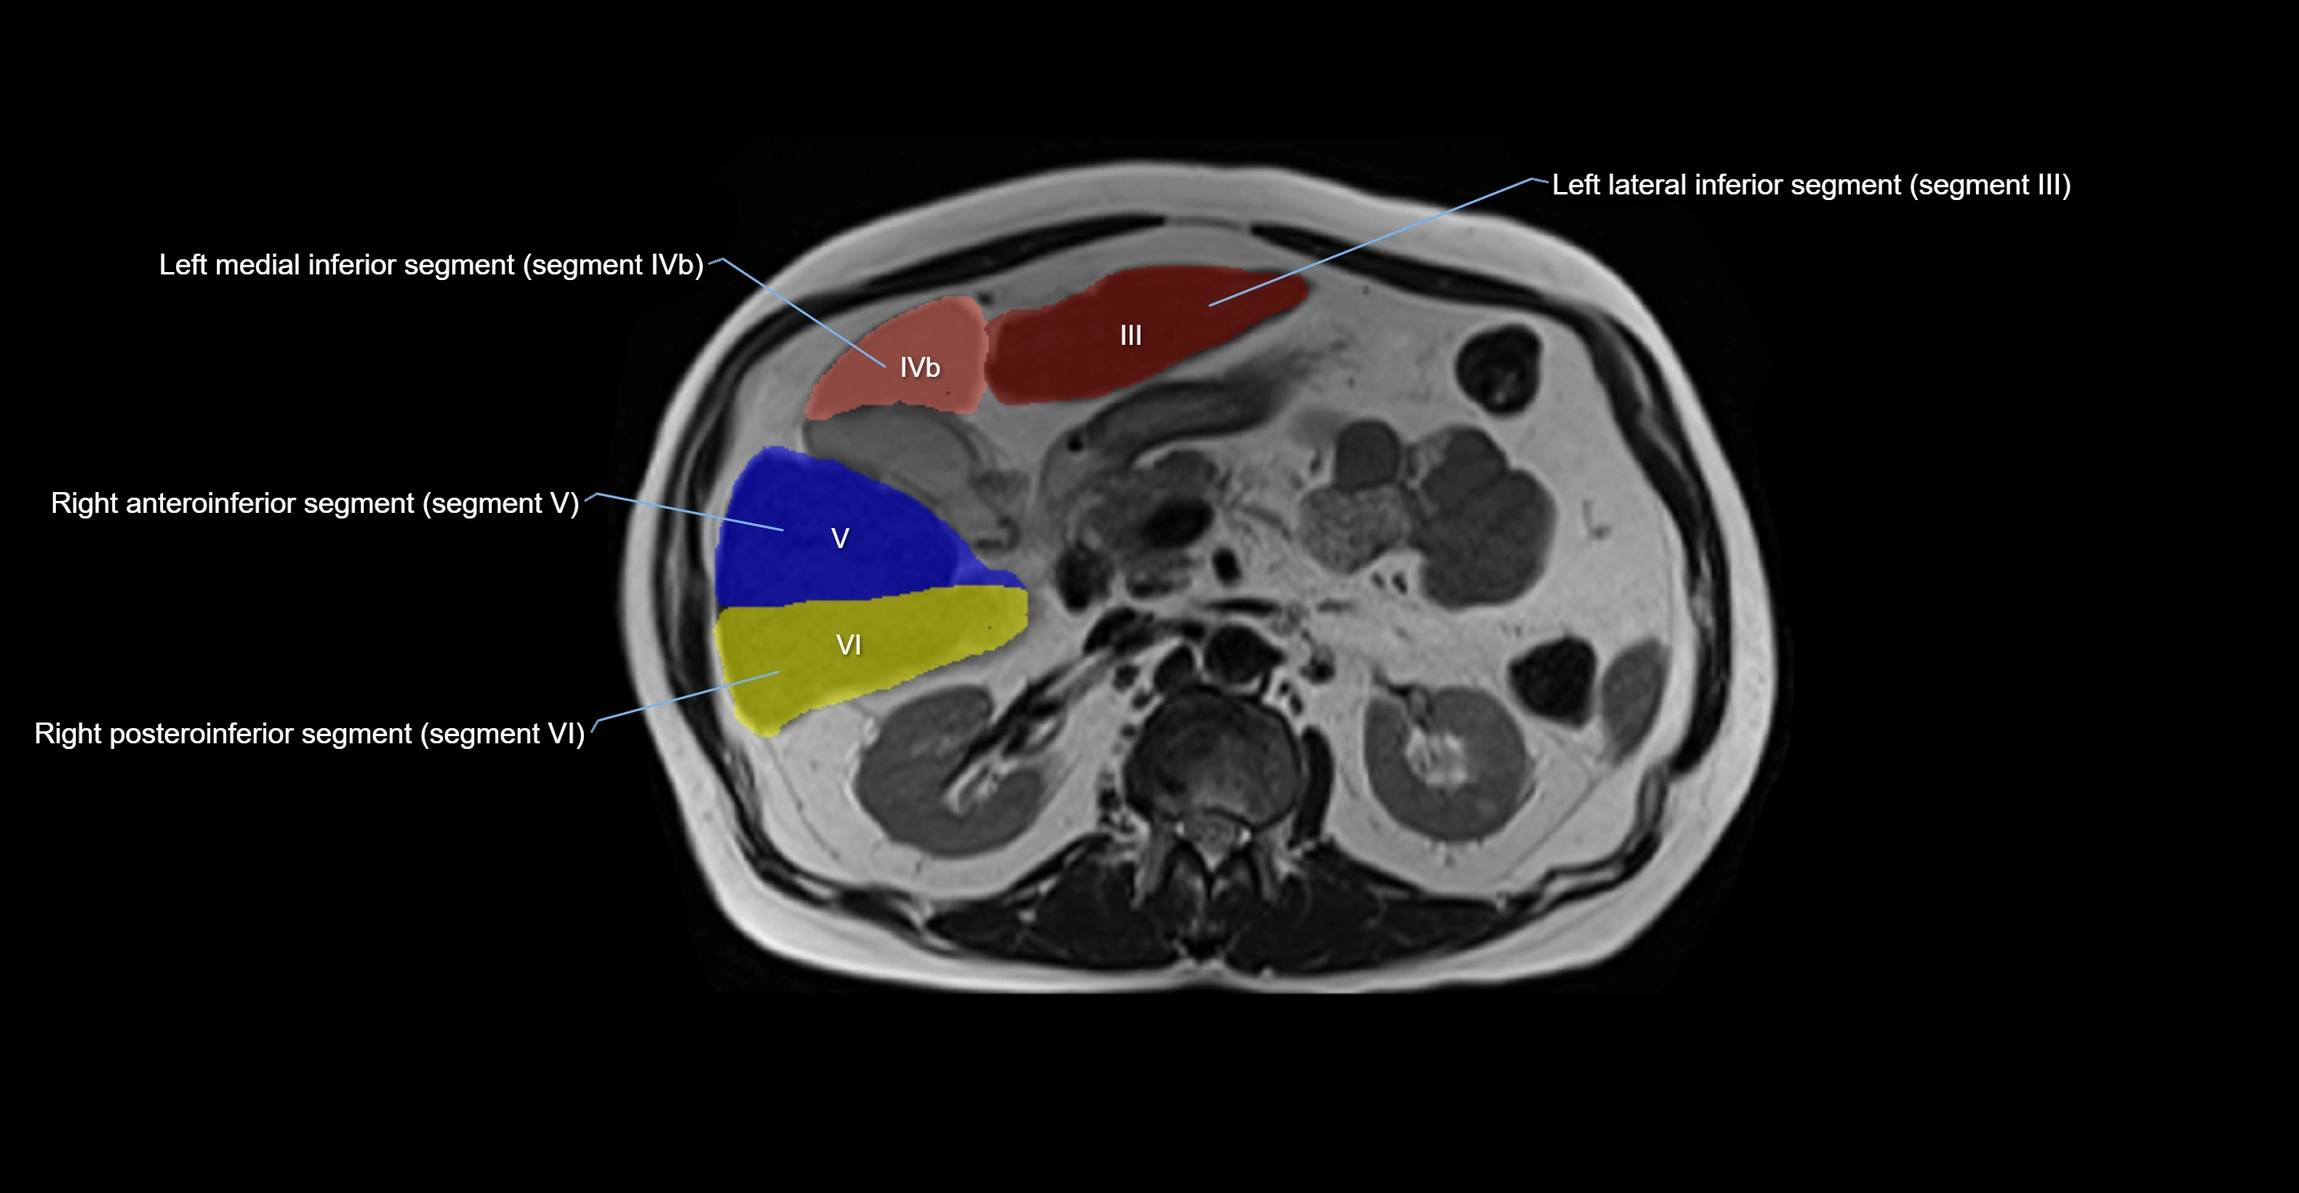

MRI image

image